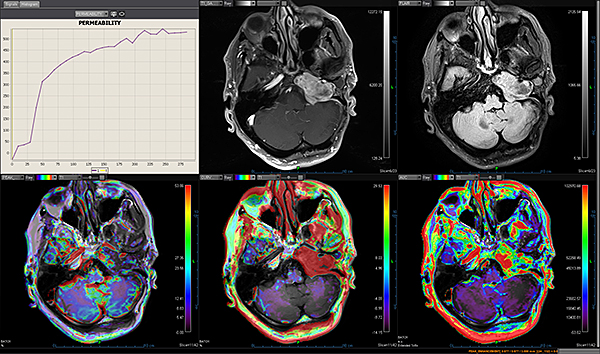

Додаток Brain Tumor Streamlined.

Додаток Brain Tumor пропонує автоматизовану покрокову обробку, включаючи кількісний мультипараметричний аналіз. Ця програма також включає оптимізований алгоритм корекції витоку контрастної речовини для підвищення точності оцінки DSC MР-перфузії.